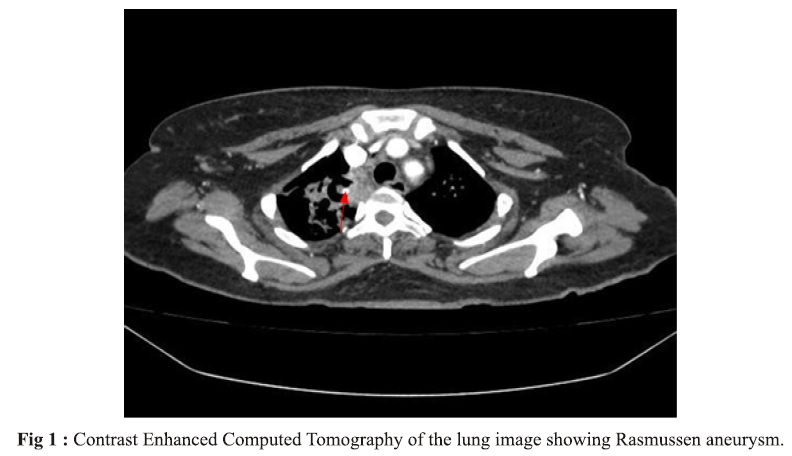

Rasmussen Aneurysm secondary to Covid-19: A case report

Finciya C Pappu, Sijin T Biju, Lakshmi R, Siby Joseph, Suith Kumar (Author)

2659-2663